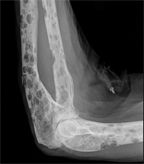

Multiple myeloma, x-ray with multiple osteolytic lesions in the forearm; source: Hellerhoff, Wikimedia Commons